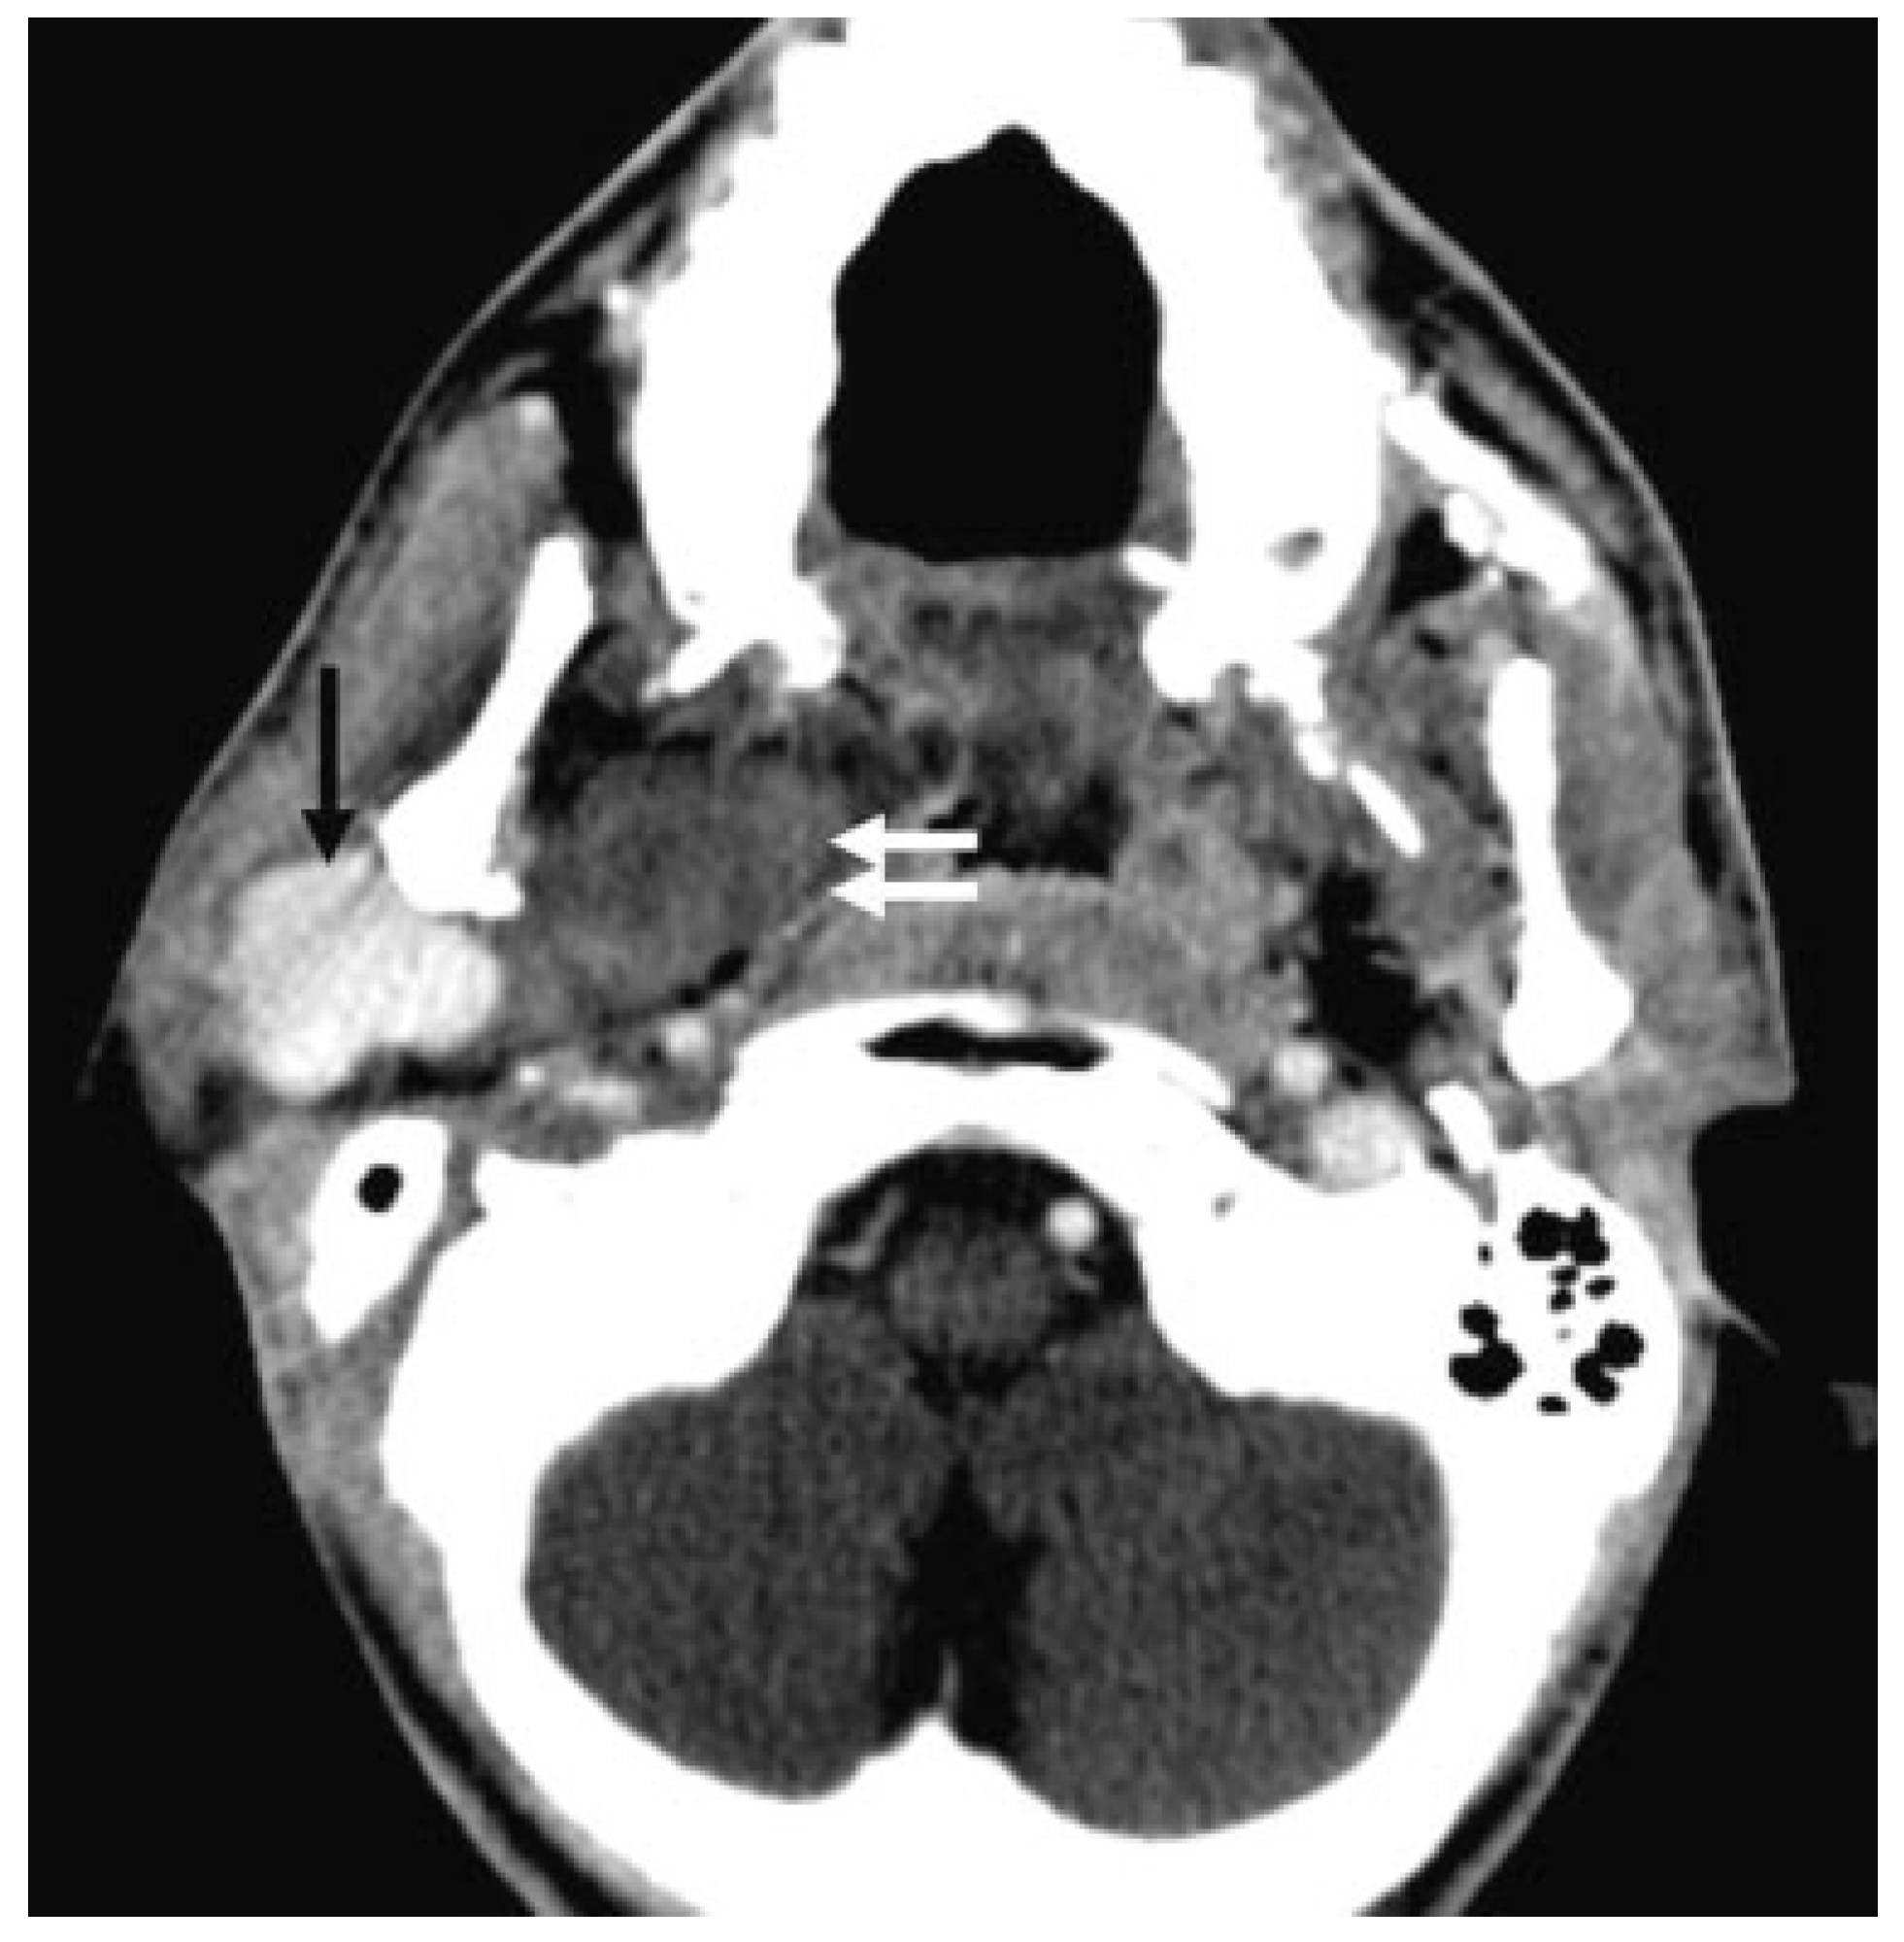

:Case Report